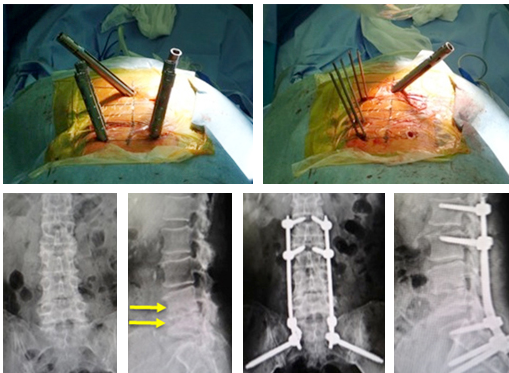

【びまんせい特発性とくはつせいこつ増殖症ぞうしょくしょう強直性きょうちょくせい脊椎炎せきついえんに対するミスト手術】

びまん性特発性骨増殖症(Diffuse Idiopathic Skeletal Hyperostosis)や、強直性脊椎炎(Ankylosing Spondylitis)という、脊椎が連続して癒合してしまう疾患があります。

問題点として、元々脊椎が癒合していない部分や、軽微な外傷による微小な骨折などで徐々に不安定性が生じ、脊髄の圧迫をきたします。ちょっとした転倒などの数ヶ月後に、重篤な神経障害を呈することもあり、注意が必要です。治療は、保存治療では改善しないケースも少なくないため、手術治療がしばしば選択されます。

当院では、大きな切開を加えること無く、経皮的椎弓根スクリューを用いた特殊な方法で脊椎を安定化させるミスト手術を積極的に行っております。

図 (上)連続性に骨が癒合している間に骨が癒合していない部分があり、同部位で持続的な不安定性が生じて、脊髄が圧迫されています。

(下)経皮的椎弓根スクリューを用いたミスト手術で、大きな切開を加えること無く脊椎を安定化し、神経症状は著明に改善しました。